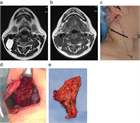

1. 頸部嚢胞性疾患は、先天性と後天性に区分される。先天性疾患は、小児・若年者の疾患であり、発生に沿った局所部位に波動を伴う腫瘤として確認される。これらの病態の理解には発生学の知識が必要になる。また、実際に臨床上の「嚢胞性」のなかに、画像上は充実性にみえる場合(蛋白濃度が高い内容液や血液を含む嚢胞)や、充実性腫瘍(脂肪腫は柔らかいため嚢胞性腫瘤の理学的所見を呈している)も含まれる。ただ、一般的に嚢胞とは分泌物が袋状に貯まる病態を指す( G)。

1. 頭頸部画像診断上、位置、形状、大きさ、壁の性状、境界、隔壁の有無、充実性部分や石灰化の有無、発生部位と進展範囲などが評価される。

1. 頸部嚢胞性疾患は、多くが先天性疾患であり、頸部正中と側頸部に発生する嚢胞に分類される。